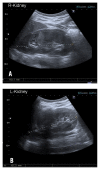

Case presentation: We describe a 5-month-old asymptomatic female patient with bilateral diffuse nephrocalcinosis and nephrolithiasis. Laboratory and genetic findings confirmed PH1. She was promptly administered conservative treatment consisting of high fluid intake, calcium oxalate crystallization inhibitors, and pyridoxine. Nephrocalcinosis and urolithiasis disappeared after 2 years of treatment. As far as we know, this is a unique case of a patient with an I244T/null mutation diagnosed after the neonatal period and with normal renal function, who remained asymptomatic during an 18-year follow-up. This case is also unique because of the long-term therapeutic success.